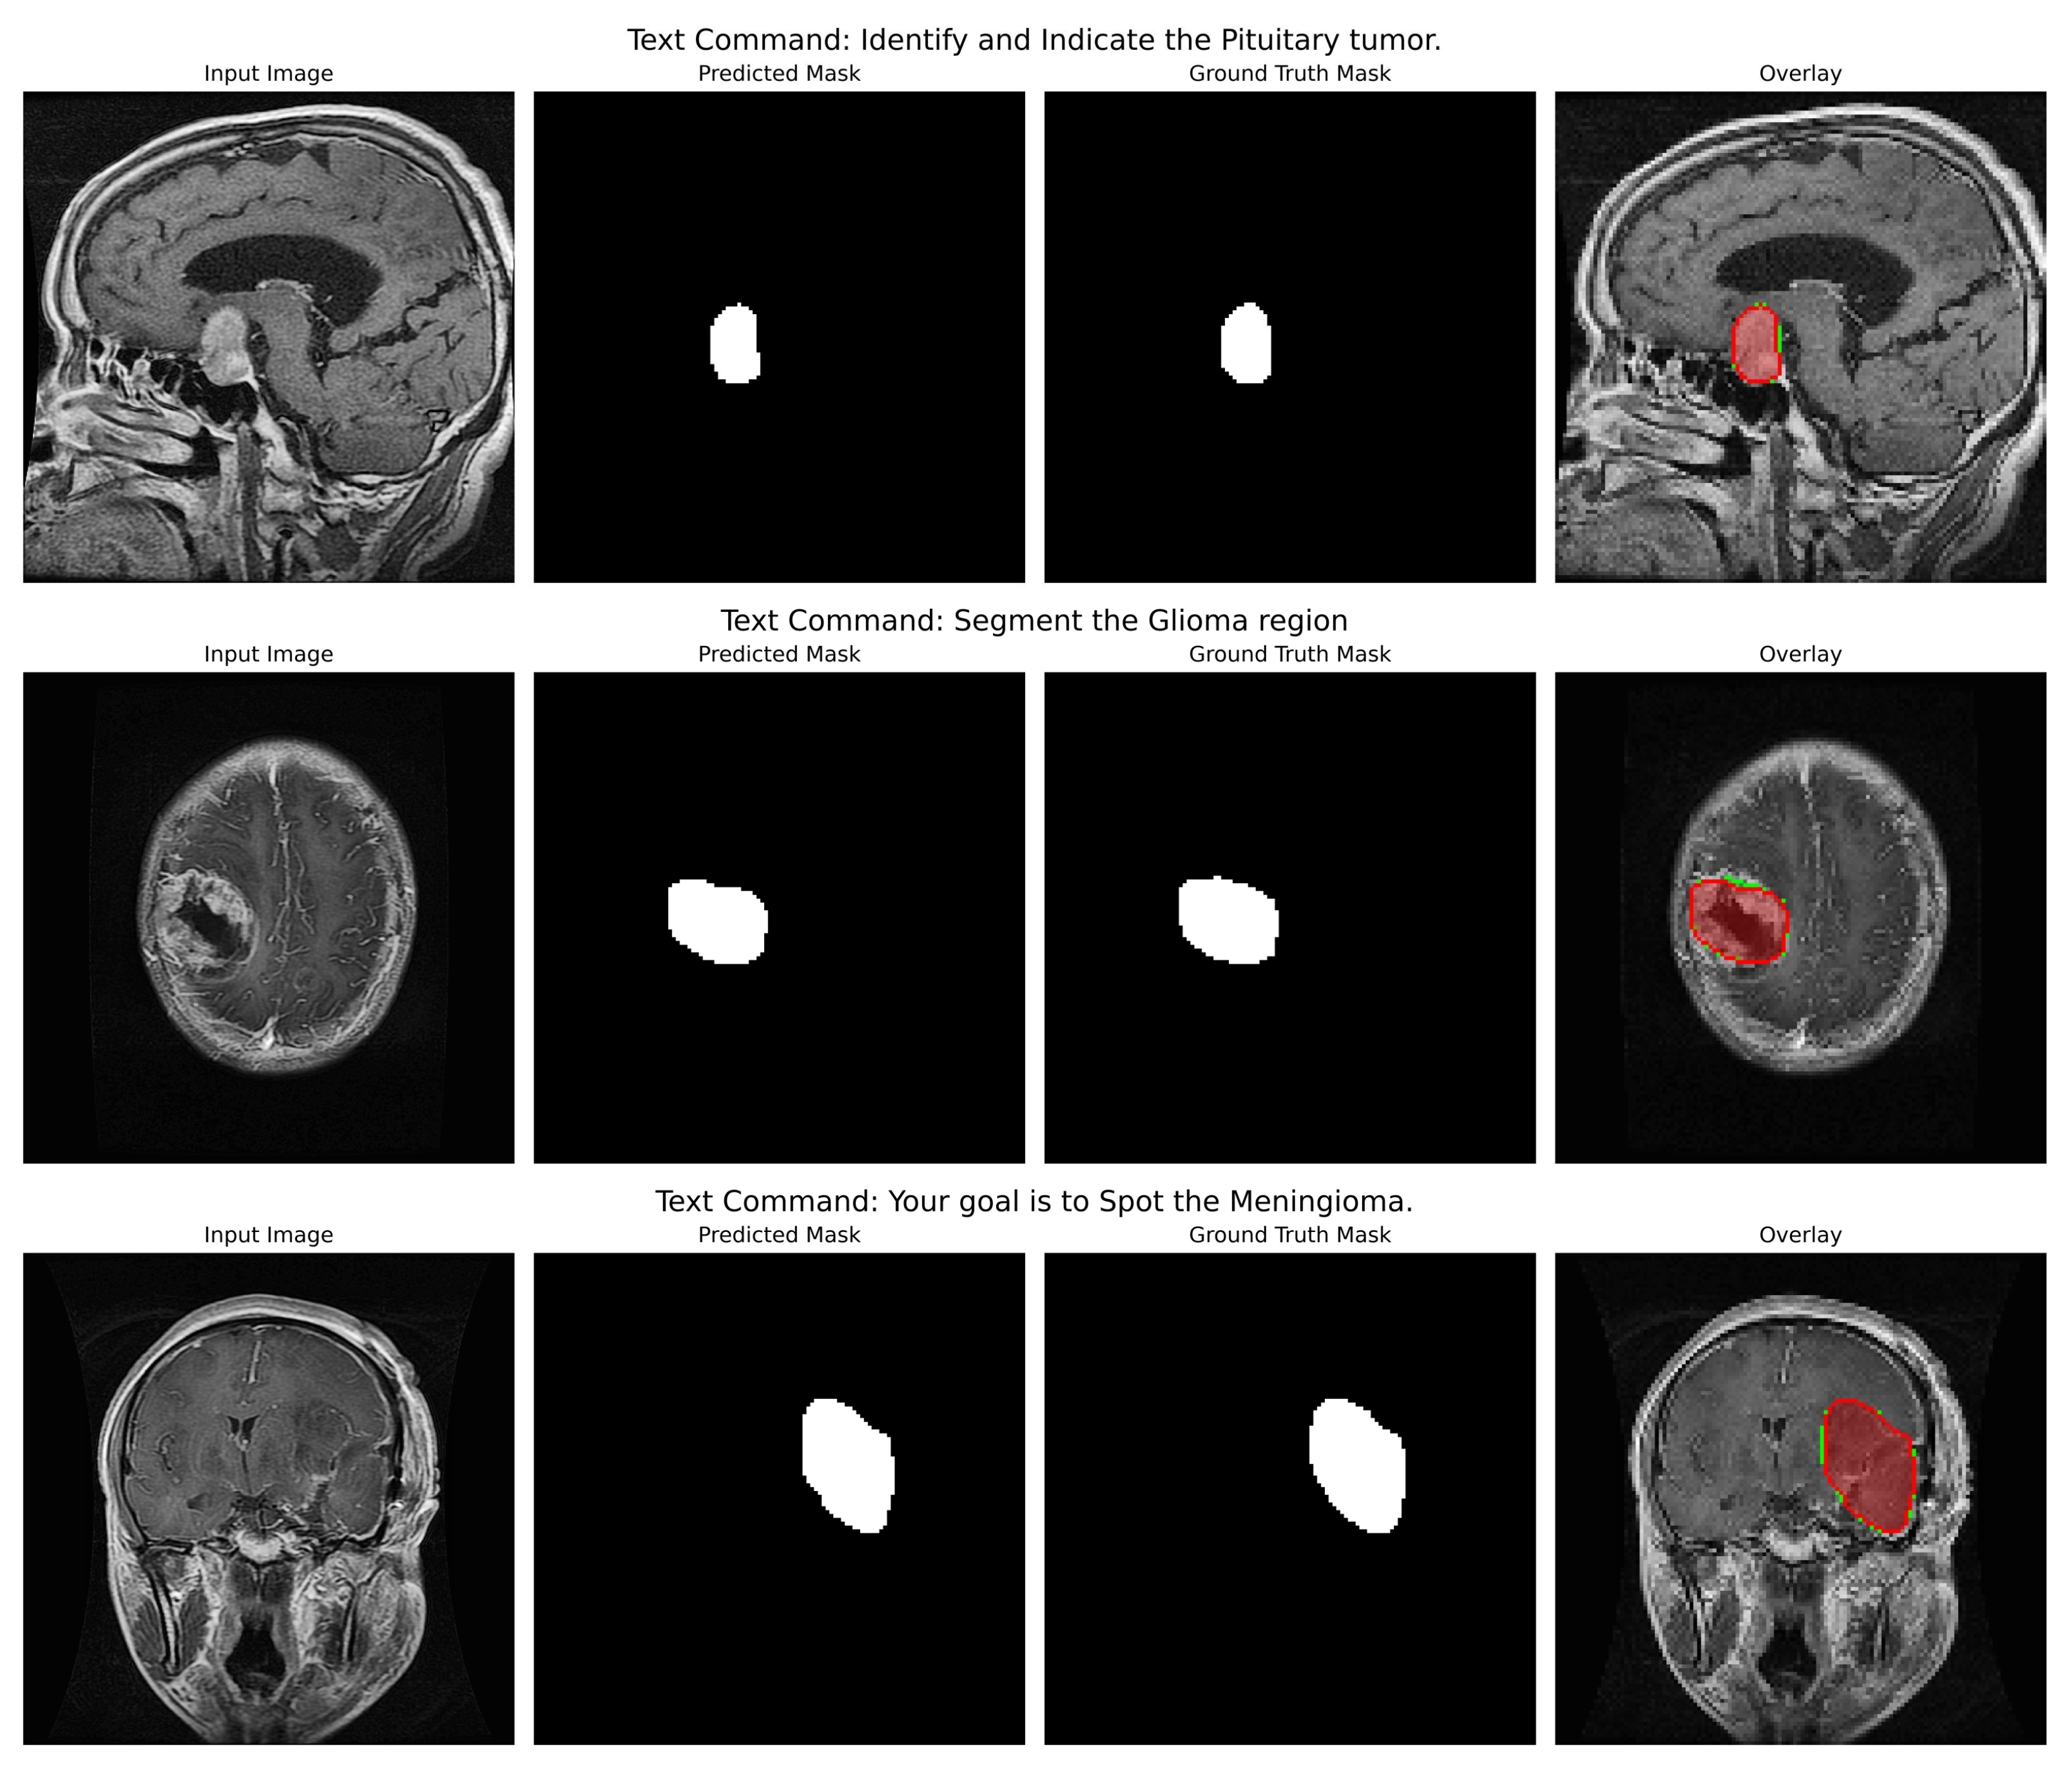

Qualitative Analysis: The qualitative figures (refer to Figure 4) provide a strong indication of the model’s potential utility in the clinic as well as its capacity to convert abstract linguistic instructions to anatomically accurate segmentations. Those four different examples in the figure demonstrate the model’s vast ability to change. One of the pairs illustrates how the command “Segment the Glioma region” produces a segmentation mask that not only visually looks like the ground truth but also accurately represents the irregular, infiltrative margins of gliomas in the context of the surrounding edematous brain parenchyma. The overlay confirms that the model both located the lesion and described its complex and varied shape (which is extremely important for surgical planning) correctly.

In the second pair of images, the input instruction “Your goal is to Spot the Meningioma” has been effectively used to isolate the meningioma, a tightly packed, encapsulated tumor (a tumor with a drastically different shape from the glioma). The resultant mask features a clear, smooth border along the tumour capsule while the adjacent normal tissue is left out, thus serving as a perfect example of the model’s capability to utilize semantic cues for fine-grained discrimination.

Indeed, this direct comparison of the two tumor types (prompted under different linguistic cues) dramatically illustrates that the model is not learning a static mapping from image to masks but is performing a contextual, semantic reasoning task. That specific performance verification against real-world clinical scenarios provides a strong foundation to the backbone hypotheses supporting the multimodal approach, such that with the same architecture, accuracy can be maintained for absolutely different pathologies based on pure text input. Even in cases where the morphology differs quite significantly, the similarity between predicted mask and ground truth adds credence to the generalization strength of this approach; that is, it should act like a kind of general, prompt-controlled diagnostic assistant, be it by bringing down the retraining of models to new applications, making a truly more interactive human-AI experience in the clinical workflow, or even both.